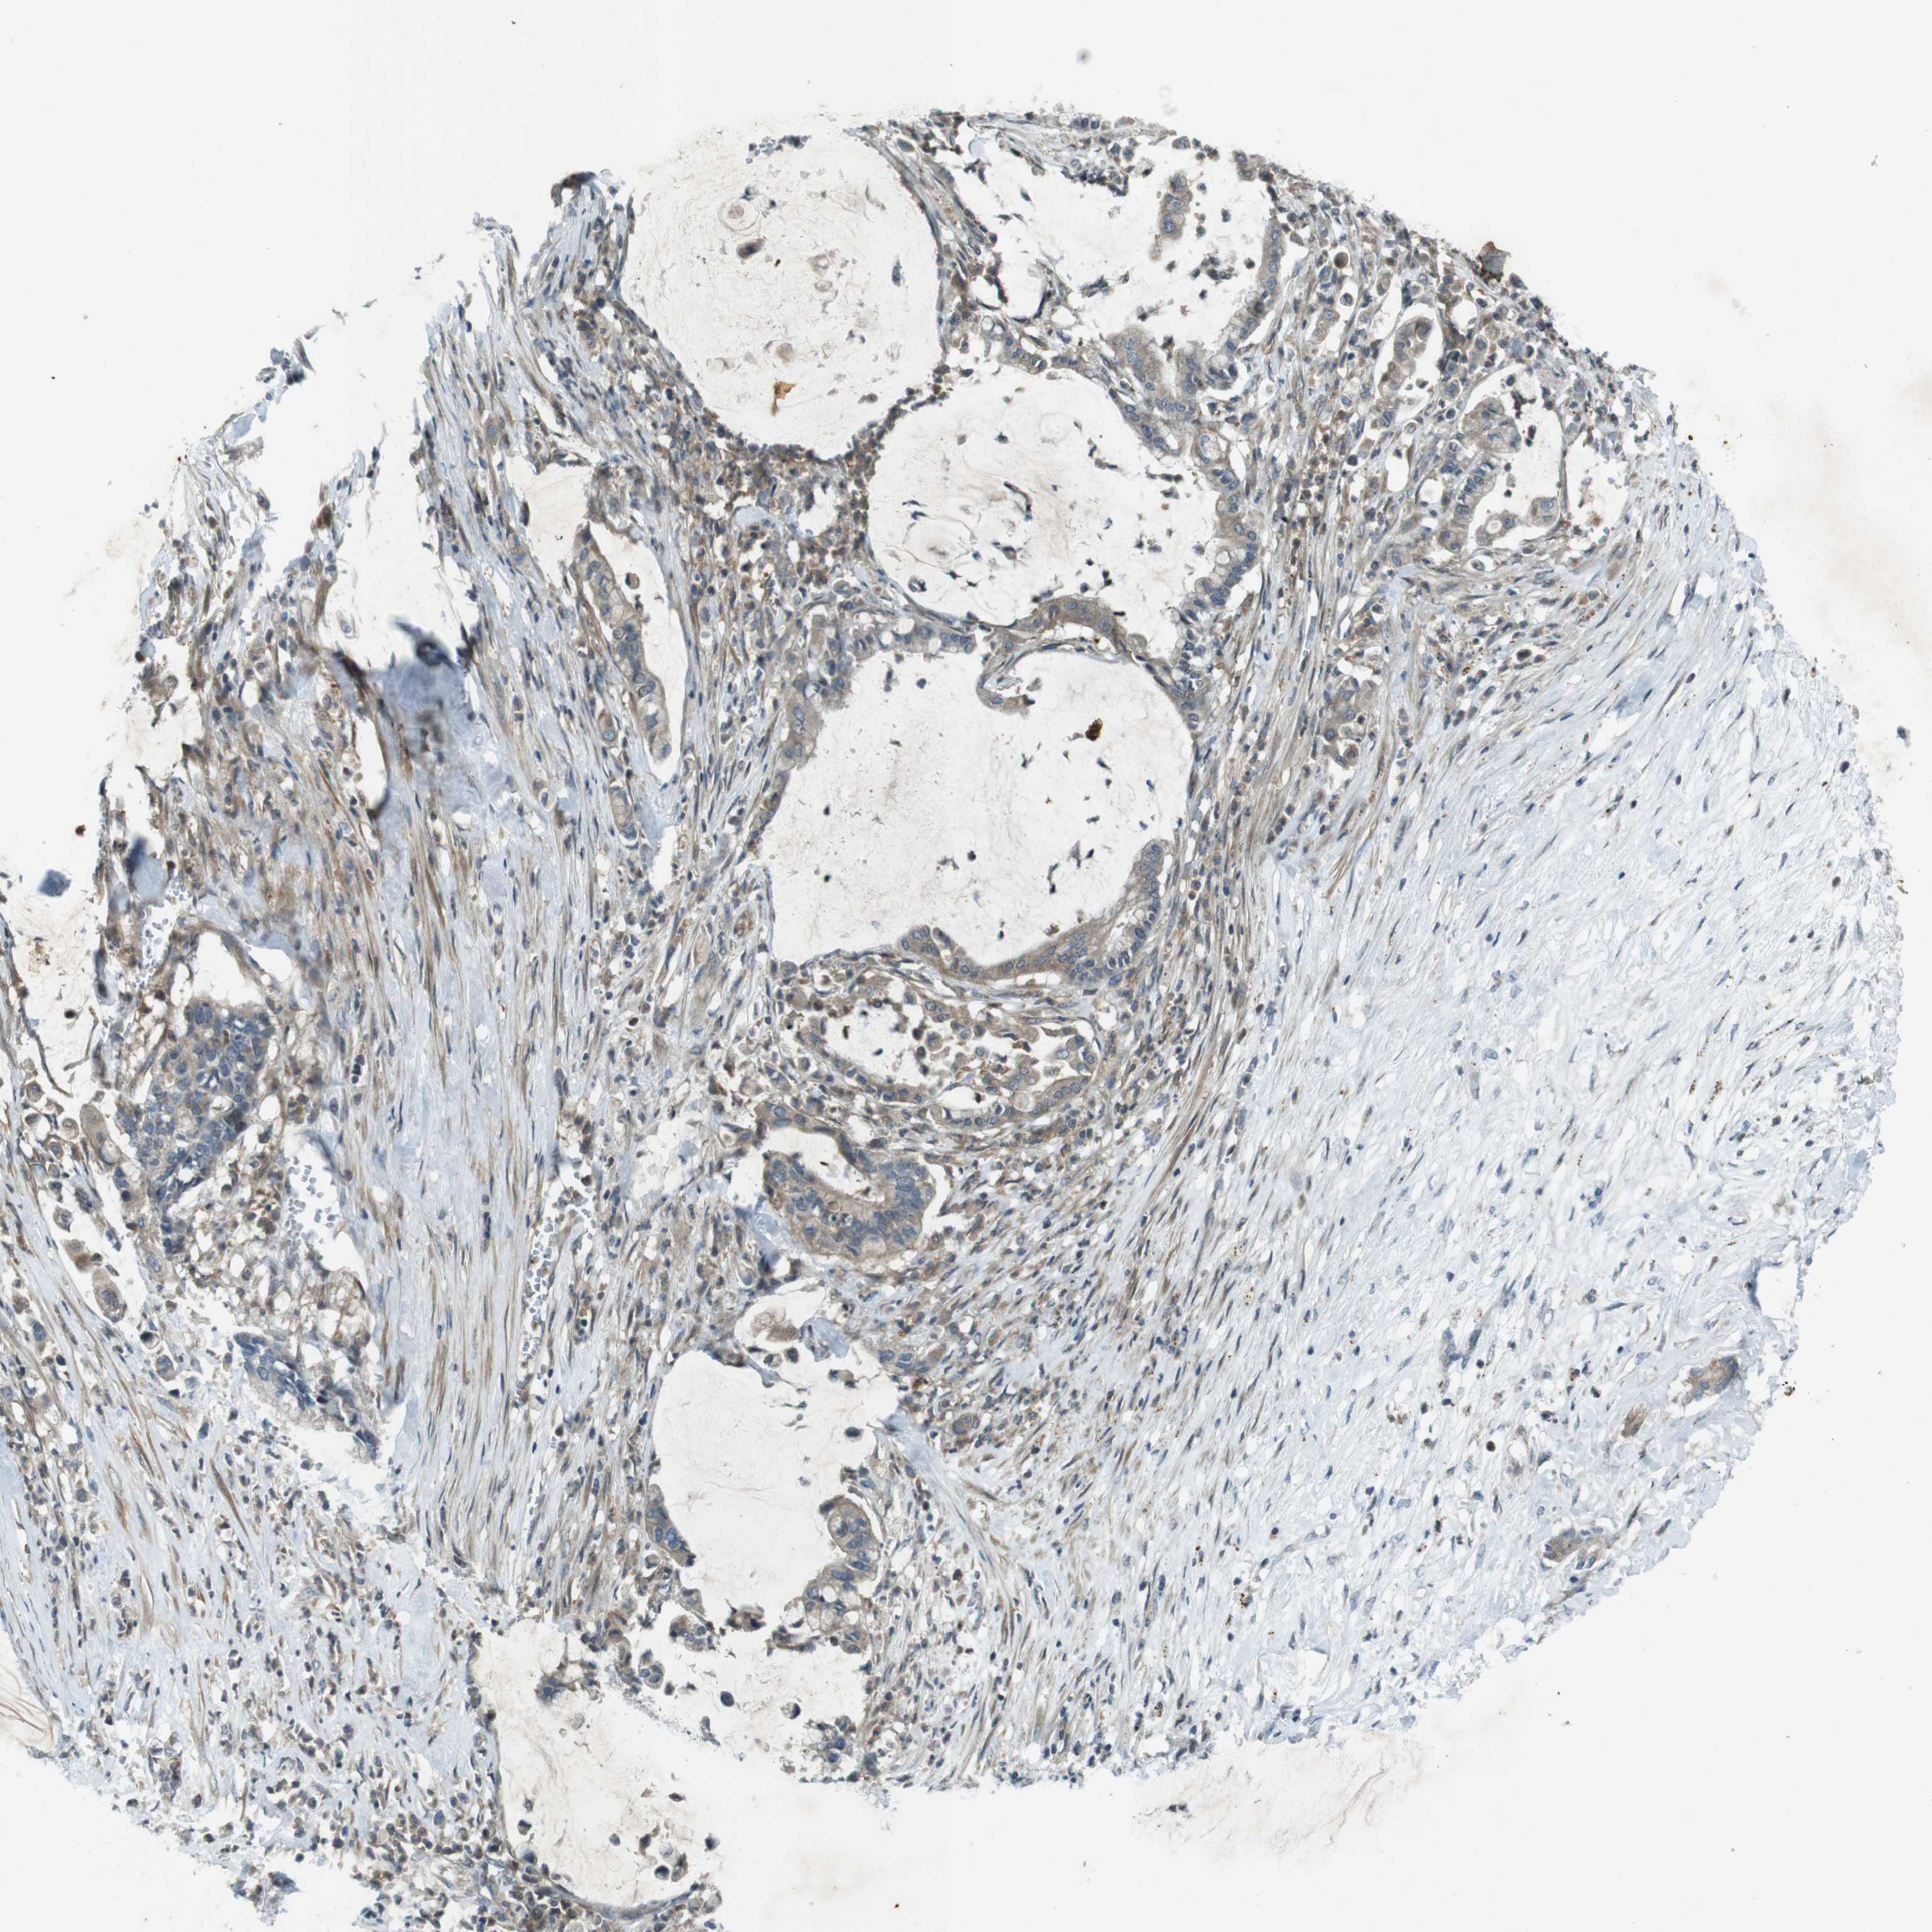

PANCREATIC CANCER - Protein expressioni

A mouse-over function shows sample information and annotation data. Click on an image to view it in a full screen mode. Samples can be filtered based on level of antibody staining by selecting one or several of the following categories: high, medium, low and not detected. The assay and annotation is described here.

Note that samples used for immunohistochemistry by the Human Protein Atlas do not correspond to samples in the TCGA dataset.

Antibody stainingi

Antibody staining in the annotated cell types in the current human tissue is reported as not detected, low, medium, or high, based on conventional immunohistochemistry profiling in selected tissues. This score is based on the combination of the staining intensity and fraction of stained cells.

Each image is clickable and will lead to virtual microscopy that enables deeper exploration of all samples and also displays staining intensity scores, fraction scores and subcellular localization as well as patient and tissue information for each sample.

Antibody HPA004835

Antibody HPA073497

Antibody CAB009321

Antibody CAB075747

Adenocarcinoma, NOS